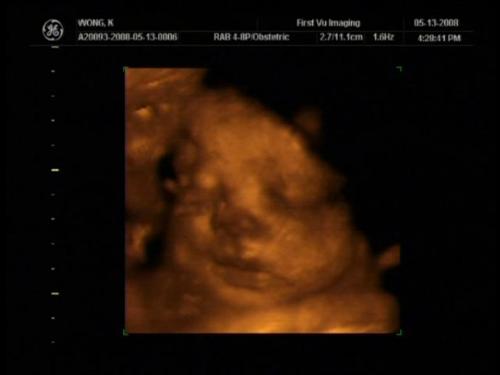

These are mine from DS. I think I was about 30 weeks (more pics in my album titled my pregnancy).

That thing by his right eye is his leg! He was breech.